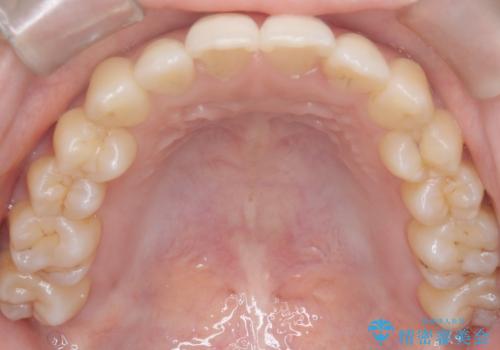

- 前歯のガタガタ(叢生)と、前歯が出ている(突出している)ことを気にされてご来院されました。精密な検査の結果、歯が並ぶスペースと、前歯を引っ込めるスペースの両方が不足していると診断。患者様のご希望に合わせ、透明で目立ちにくいインビザライン(マウスピース矯正)による治療計画を立案しました。スペースの確保は、奥歯全体を奥へ動かす遠心移動と、歯の側面をわずかに削る**IPR(歯間乳頭保護下ストリッピング)**を組み合わせて行い、前歯を効果的に引っ込めることを目指します。

今回の矯正治療では、透明なマウスピース型の装置インビザラインを使用しました。前歯を無理なく引っ込めるスペースを作るため、まず奥歯全体を後方へ移動させる遠心移動を実施。さらに、安全性が確保できる範囲で歯の側面をわずかに削るIPRを併用し、必要なスペースを確保しました。これらの処置により、前歯のデコボコが解消され、前に出ていた前歯も適切に引っ込みました。目立たない装置で治療を完結することで、叢生と突出感が解消され、機能性と審美性が向上した美しい口元を獲得していただけました。